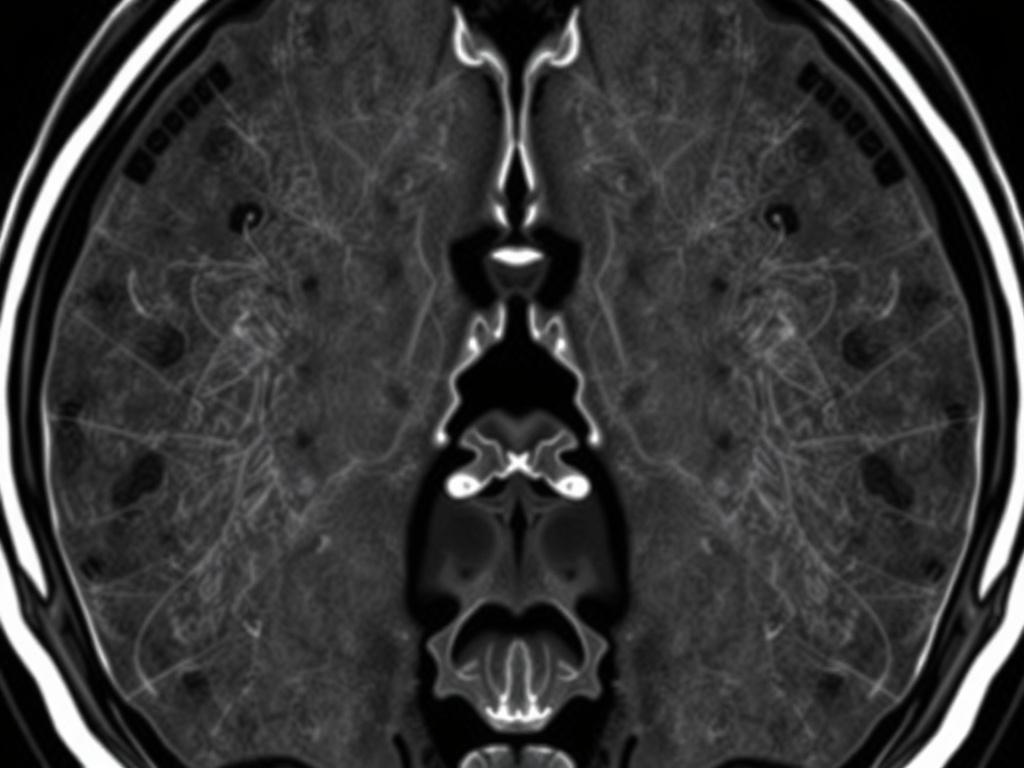

МРТ — это не просто красивая картинка. Это способ увидеть мягкие ткани: межпозвонковые диски, спинной мозг, нервные корешки, связки и костный мозг тел позвонков. В отличие от рентгена и КТ, МРТ не использует ионизирующее излучение и даёт высокую контрастность между тканями. Благодаря этому специалисты точнее ставят диагноз и планируют лечение. Здесь можно получить больше информации про МРТ отделов позвоночника.

Основные МРТ-последовательности и что они показывают

Картинки, которые вы получите, — это не просто «фото». Разные последовательности выделяют разные свойства тканей: вода, жир, патологический отёк, кровь. Понимание того, что видит врач, помогает лучше ориентироваться в заключении.

| T1 | Хорошая анатомия, жировая ткань светлая | Оценка структуры позвонков, жировой ткани, контрастного усиления |

| T2 | Жидкость и отёк светлые | Выявление грыж, отёка, пролабирующего ядра диска |

| STIR (или T2 с жироподавлением) | Подавляет жир, подчёркивает отёк и воспаление | Инфекции, травма, воспалительные процессы |